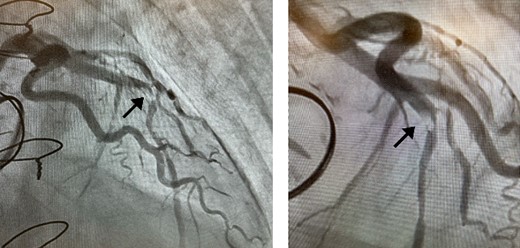

Postoperatively, an electrocardiogram revealed anterior ST-segment elevation, indicative of myocardial ischaemia. The patient then developed renal insufficiency. Given his haemodynamic stability, he was initially managed using coronary dilators and heparin. To improve renal function, coronary angiography was performed on the 10th postoperative day, which revealed a filling defect and 90% stenosis in the LAD artery (Fig. 1). Computed tomography (CT) revealed a high-density mass in the LAD artery with a mean CT value of 400 Hounsfield units (HUs) (Fig. 2). These findings indicated embolism, possibly due to a pledget from a previous surgery. A transcatheter approach was employed to remove the embolus, which was successfully extracted using a snare (Fig. 3a). Angiographic assessment revealed that the previously stenotic LAD demonstrated full perfusion, consistent with a thrombolysis in myocardial infarction (TIMI) flow grade of 3 (Fig. 3b). The patient recovered from catheterization without complications.

Coronary angiography detected 90% stenosis in the LAD artery; the arrow indicates the filling defect.